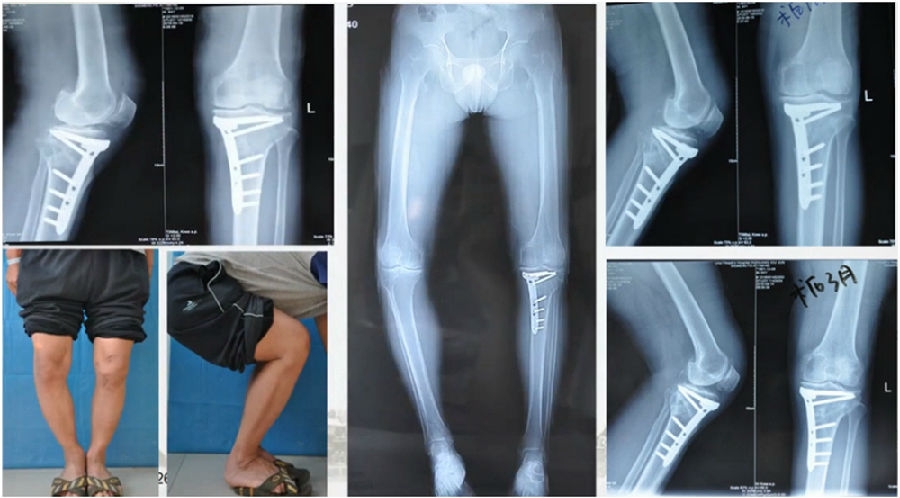

结合影像学来看,该患者单纯用闭合截骨或开放截骨,对肢体均有影响,所以决定采用混合型截骨。术中混合截骨旋转中心选在内外1/3处,先做闭合楔,然后顺势将开放楔敲开,达到术前设计的目标力线。术后随访力线达到要求。

术后X线

术后检查证实达到了术前预期的手术效果,关节线达到了平行,半脱位得到矫正,同时关节线和地面水平。病人行走达到了理想的效果。

患者术后4个月截骨愈合,膝关节稳定维持得非常好。

术后4个月